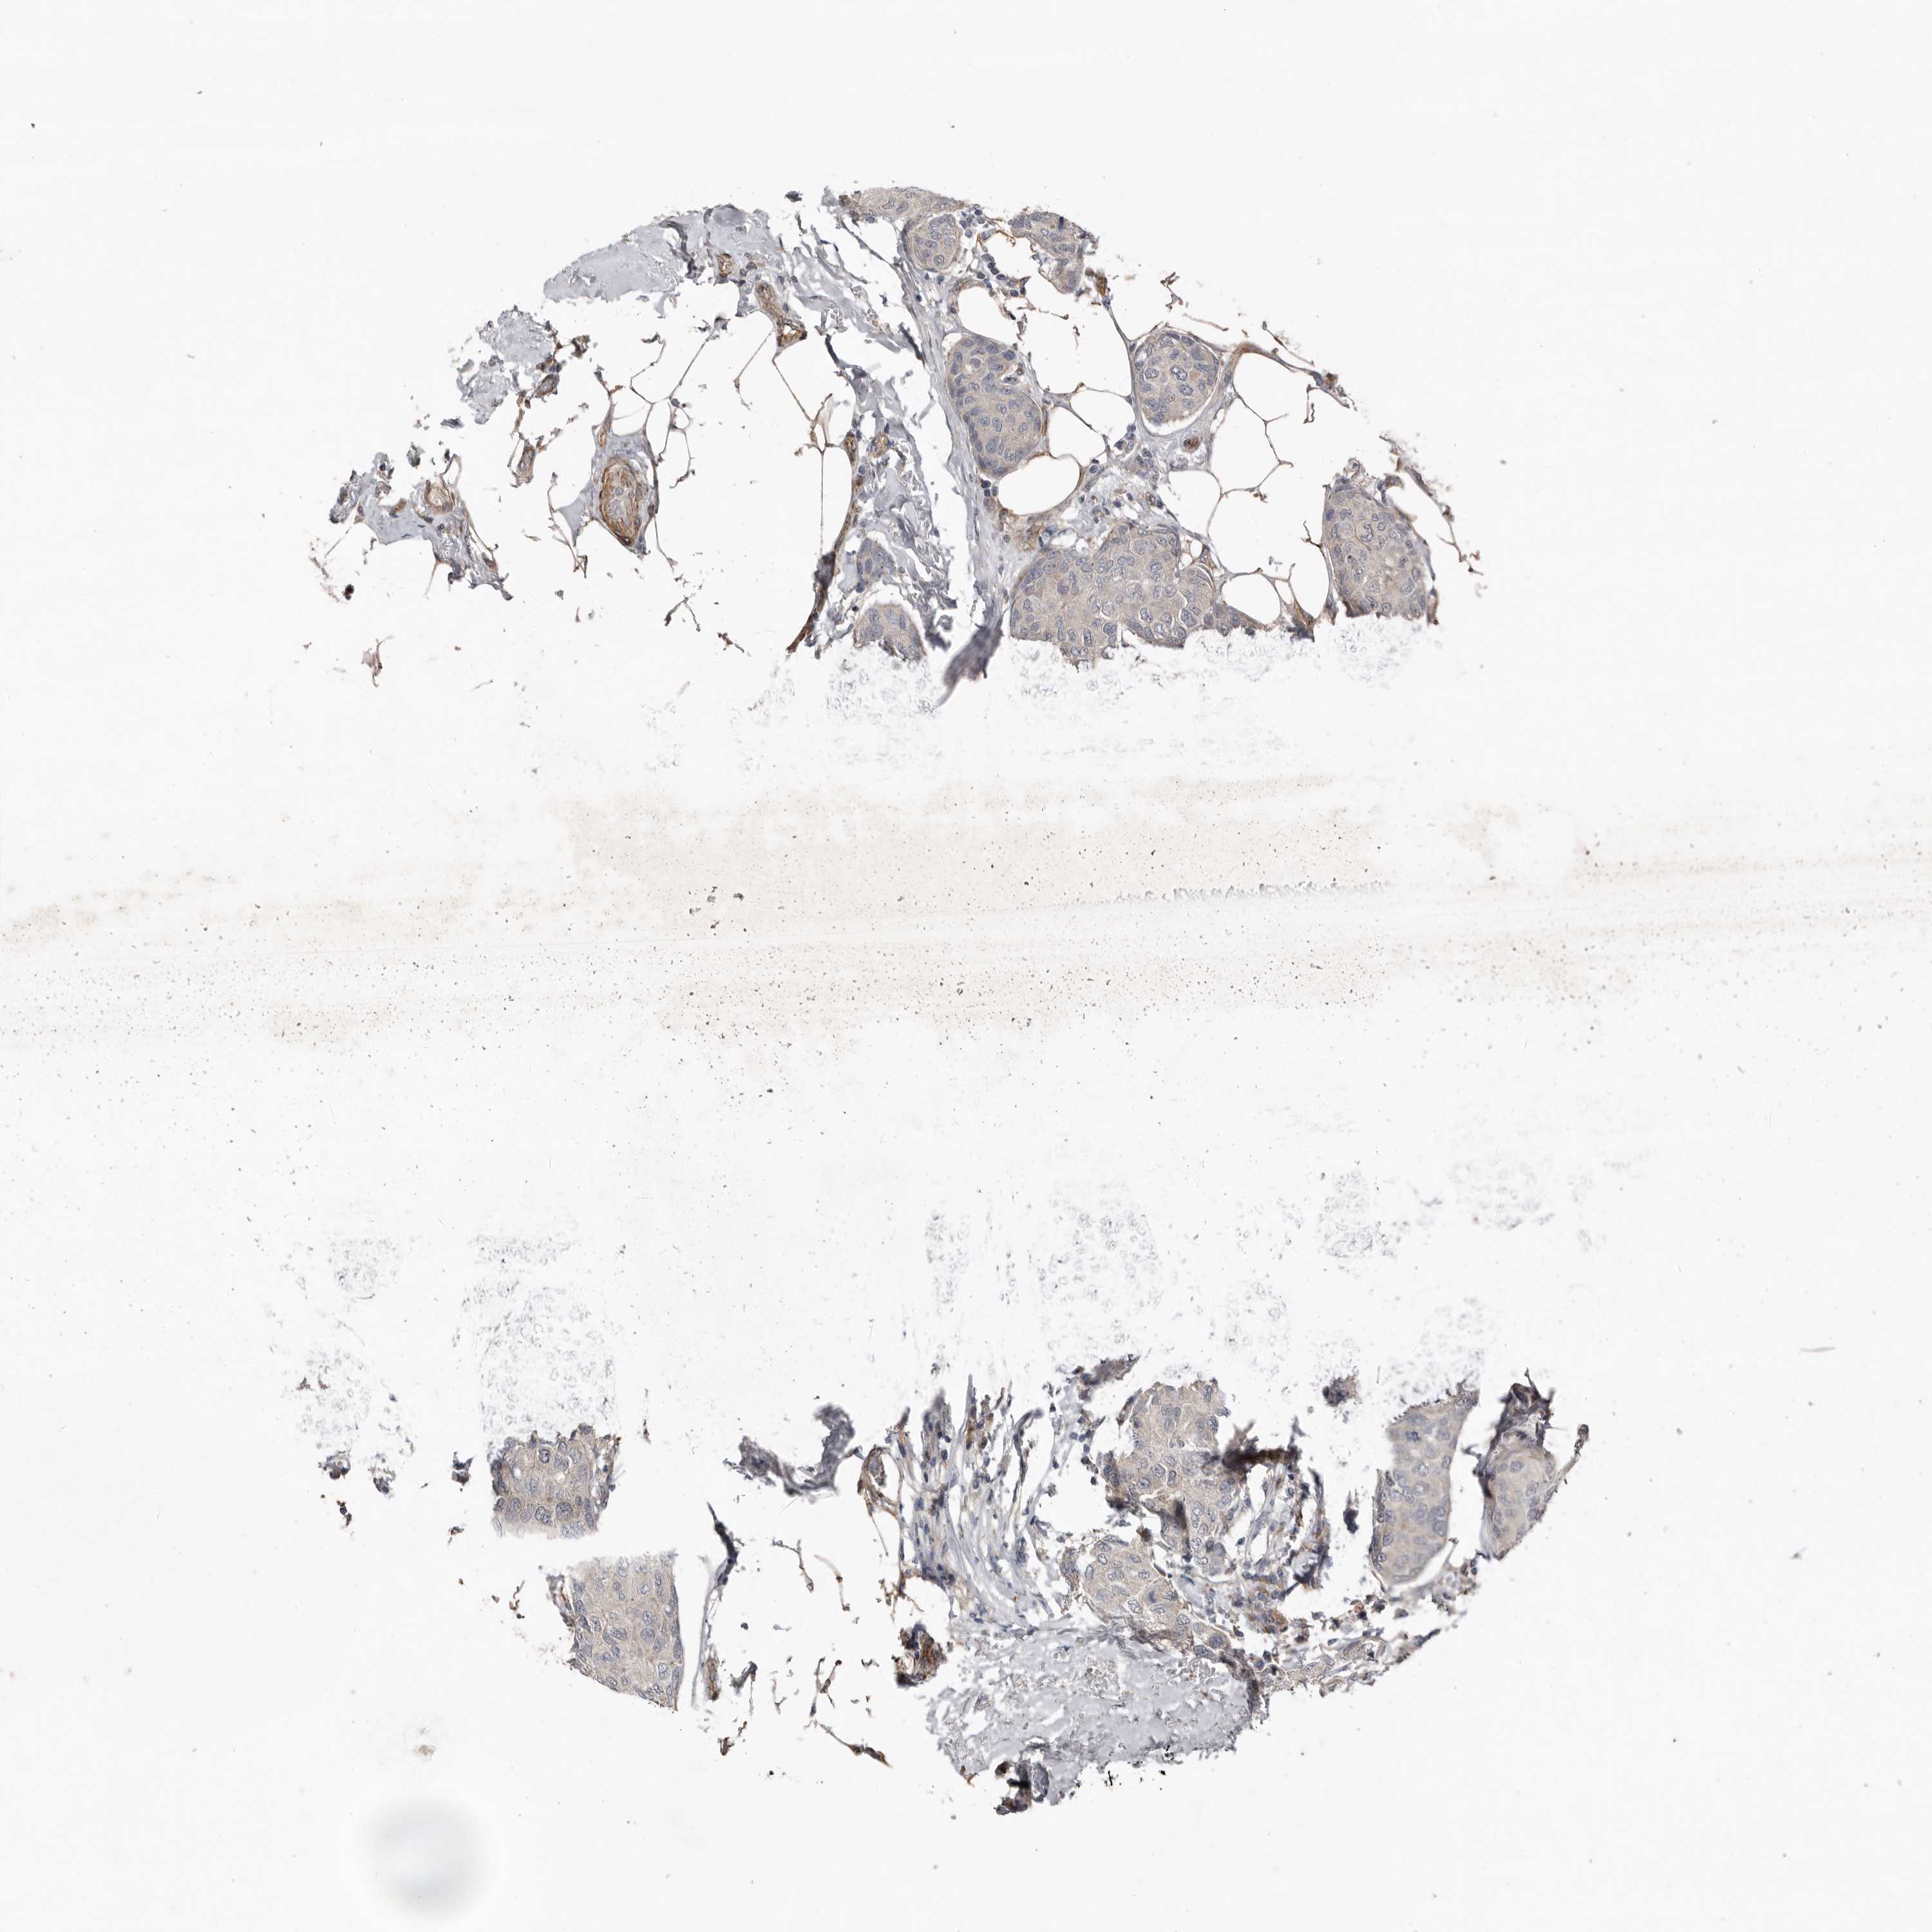

CANCER BREAST CANCER Show tissue menu

BRCA TCGA BRCA VALIDATION PROTEIN EXPRESSION

ANTIBODIES

AND

VALIDATION